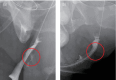

Case presentation: A transgender man underwent surgery at a private clinic and experienced recurrent complications. Subsequent examination at another clinic and our hospital revealed limited medical records, complicating our understanding of this case. After a detailed investigation, the urethrocutaneous and urethrovaginal fistulas were identified and addressed by joint urologists and plastic surgeons, resulting in no recurrence after 1 year.